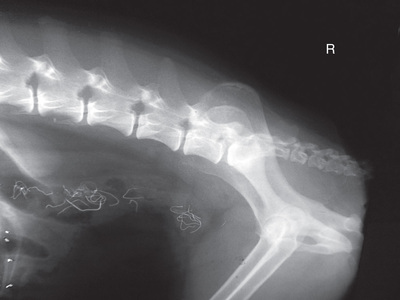

Fig. 20.24 is a mystery radiograph. Review it and answer the question presented with it.